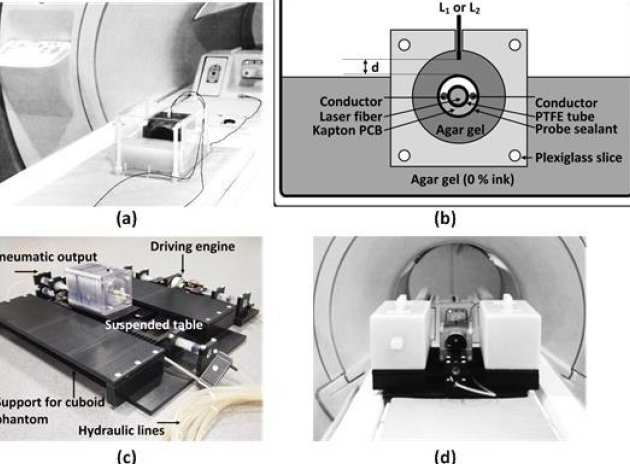

Evi Kardoulaki, Richard Syms, Ian Young, Marc Rea and Wady Gedroy

We have investigated whether local flexible micro-coils integrated with ablation catheters can improve the temperature accuracy during MR-thermometry in liver laser interstitial thermal therapies (LITTs). A liver-mimicking gel phantom was used to assess micro-coil derived image quality and sensitivity and ensure such coils can provide adequate FOV and resolution for the target application at 3T. The impact of liver motion was assessed using a MR-compatible hydraulic motion simulator. The thermal profile of a static phantom during an Nd:YAG laser ablation was monitored using reference-based PRF MR-thermometry and the robustness of the method under respiratory gating was evaluated on an un-heated phantom. The results were compared with the best locally available array coil for LITTs. Micro-coils improve the temperature accuracy by 1.5-10 times in a radius matching typical lesion dimensions and enable 1 mm image resolution. The resolution can be maintained during motion by using short acquisition time sequences while the SNR remains sufficient for accurate MR-thermometry. The temperature error on the un-heated phantom under respiratory gating does not exceed 1oC.

|---|

| a) Arrangement for the static SNR and MR-thermometry comparison studies, (b) schematic of an axial thermometry slice, c) hydraulic simulator of liver motion due to breathing and (d) complete arrangement for the assessment of motion artefacts. |

| a) Radial SNR profile of the thermometry baseline image, b) respective radial temperature standard deviation; c) and d) Comparison of MR-inferred transient temperatures with the fluoro-optic readings. |